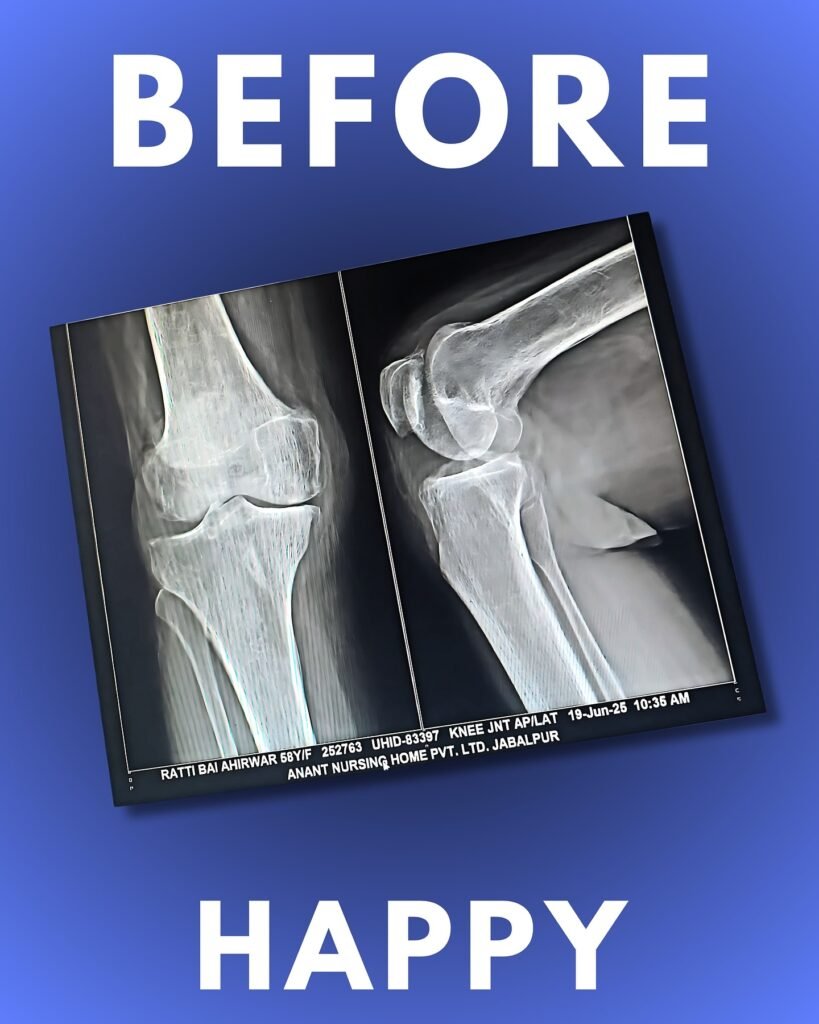

Knee replacement, also known as knee arthroplasty, is a surgical procedure that helps restore function and relieve pain in a knee joint damaged by arthritis or injury. The procedure involves resurfacing the ends of the bones with high-quality metal and plastic components to ensure smooth movement and long-term comfort. It is often recommended for patients whose quality of life is significantly affected by severe knee pain, stiffness, or reduced mobility, especially when conservative treatments no longer provide relief.

Various types of arthritis can damage the knee joint, including osteoarthritis, which causes the gradual wear and tear of joint cartilage; rheumatoid arthritis, an autoimmune condition leading to inflammation and stiffness; and traumatic arthritis, which results from injury and cartilage damage.

Knee replacement, also known as knee arthroplasty, is a procedure performed to replace the damaged parts of the knee joint with high-quality artificial implants. This surgery is recommended for patients suffering from severe arthritis or knee injuries. Dr. Nachiket Pansey, the best orthopedic surgeon in Jabalpur, ensures precision and long-lasting results through advanced surgical techniques.

Patients with persistent knee pain, stiffness, swelling, or difficulty in walking due to arthritis or joint damage can benefit from this procedure. If conservative treatments like medicines or physiotherapy fail, Dr. Nachiket Pansey, one of the top orthopedic doctors in Jabalpur, may recommend knee replacement for better mobility and pain relief.